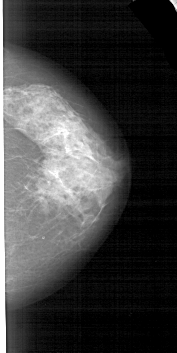

A_1553_1.LEFT_CC

LEFT_CC LINES 5176 PIXELS_PER_LINE 2551 BITS_PER_PIXEL 12 RESOLUTION 43.5 OVERLAY